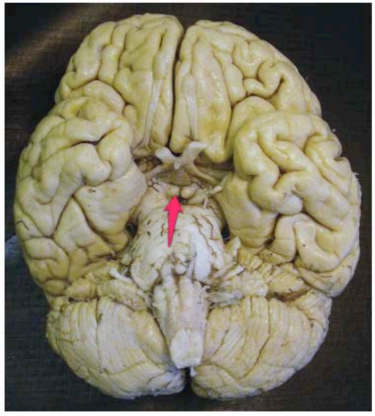

medulla oblongata

mesencephalon

tonsilla cerebelli sin.

pyramis sin. medullae oblongatae

corpus mamillare dex.

a. basilaris

pons

crus cerebri Dex.

Vermis cerebelli

hemisphaerium dex. cerebelli

hypophysis

tractus olfactorius dex.

bulbus olfactorius